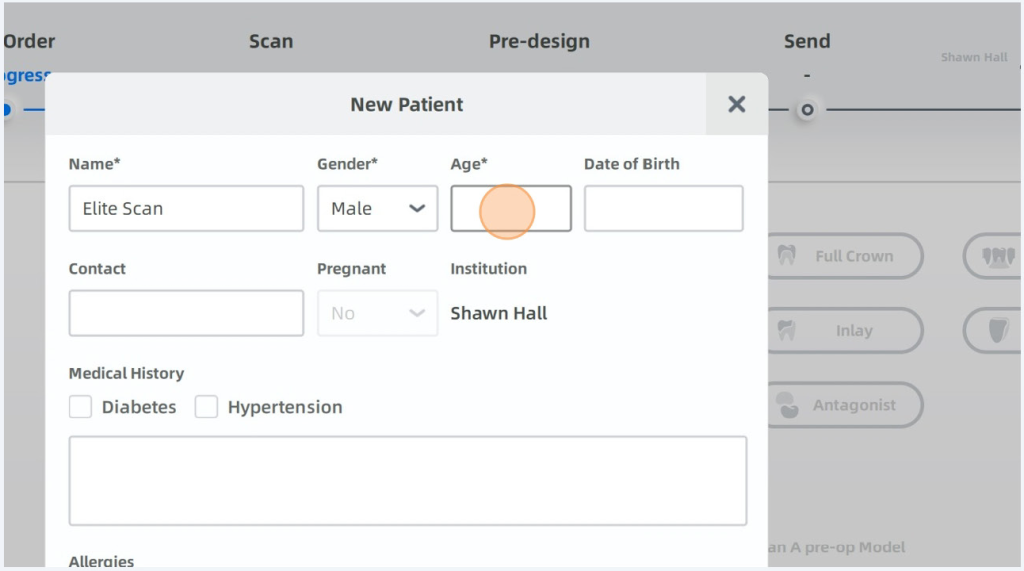

Enter Patients Name, Gender and Age required DOB optional

Click Confirm When Done